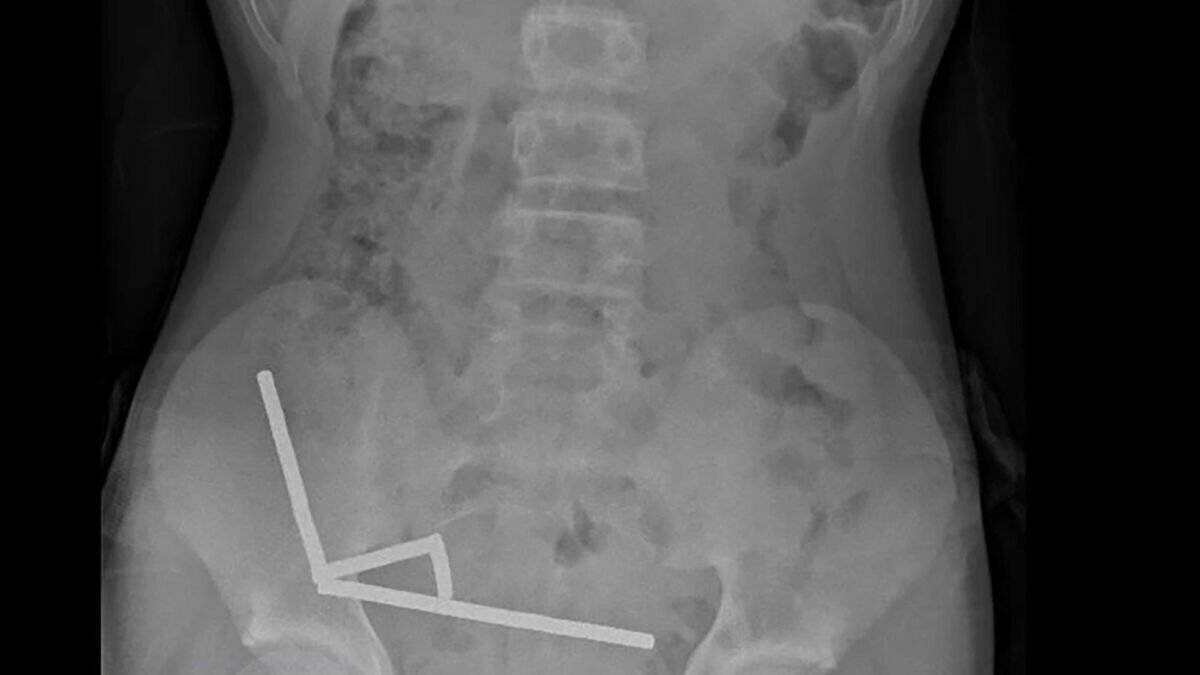

Après avoir souffert de douleurs abdominales pendant quatre jours, l’adolescent a été transporté à l’hôpital de Tauranga, sur l’île du Nord. « Il a avoué avoir ingéré entre 80 et 100 aimants puissants au néodyme, de 5x2mm environ, une semaine plus tôt », indique un rapport des médecins de l’hôpital, publié dans le New Zealand Medical Journal (NZMJ). Ce type d’aimants, interdit en Nouvelle-Zélande depuis janvier 2013, aurait été acheté sur Temu. Les médecins ont déclaré que la pression exercée par les aimants avait provoqué une nécrose dans quatre zones de l’intestin grêle et du gros intestin du garçon. Il a été opéré afin que l’on lui retire les aimants et les tissus nécrosés, et il a pu rentrer chez lui après huit jours à l’hôpital. L’article explique qu’une intervention chirurgicale à la suite de l’ingestion d’aimants peut entraîner des complications, telles qu’une obstruction intestinale, une hernie abdominale et des douleurs chroniques.

Adolescent opéré après ingestion d’aimants néodymes